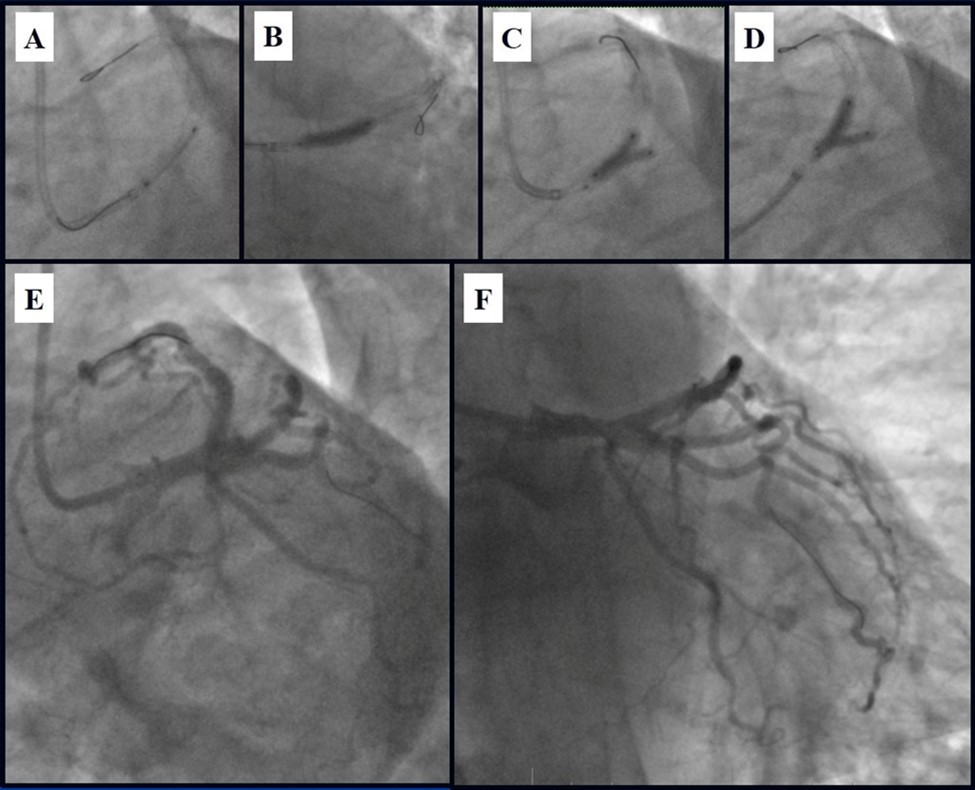

Due to financial problems the second stage was performed after 3 months (during this time the patient solved his financial problems). CAG revealed patent stents in LAD (Figure 7), and 60-70% restenosis by BMS in RCA (Figure 8). In-stent restenosis was treated by plain old balloon angioplasty (POBA), the optimal result was obtained (Figure 9). After LMCA quadrifurcation balloon predilation, 2.5×26 mm DES (Resolute Integrity, Medtronic) was implanted in the IMA, using a modified balloon mini-crush technique. The stent was minimally protruded in the LMCA and its edge was crushed by preloaded MB balloon. Next 2.5×30 mm DES (Resolute Integrity, Medtronic) was implanted in OM1 through the CX (first marginal and circumflex arteries in this particular case have the same ostium). The stent was protruded in the LMCA as in conventional modified balloon crush stenting technique, after stent deployment, its balloon was pulled back and overinflated, then protruded stent was crushed by preloaded MB balloon (Figure 10). 3.5×15 mm DES was implanted in the LMCA so that distal part of the stent covered ostial and proximal segments of the LAD. Sequential post-dilatations were performed using a kissing balloon technique (1. LMCA-LAD-IMA,2. LMCA-LAD-CX-1OM). After post-dilatations, through the stent implanted in CX-OM1, coronary wire and smaller diameter balloon (2.0 mm) were advanced in direction of the CX mid-segment and by balloon dilatation stent’s strut was opened (provisional stenting technique for CX). Finally, the proximal optimization technique was performed in the LMCA using a 3.5 mm diameter non-compliant balloon (Figure 11). The final angiographic image was good, the intervention ended without complications (Figure 11, Figure 12). We could not confirm the result with IVUS or OCT due to several technical and financial problems (not covered by insurance). 1 month after PCI, at regular checkout, the ejection fraction was 48%, the functional class of the Congestive Heart Failure decreased from class II-III to class I and the patient complaints have been disappeared.

Figure 11.Stenting of the LMCA quadrifurcation: A, B – Stenting of the LMCA; C –Kissing balloon post dilatation of the IMA-LMCA-LAD; D - Kissing balloon post dilatation of the CX-OM1-LMCA; E, F - angiography result.

Figure 12.Schematic presentation of the implanted stents, “spider” projection.